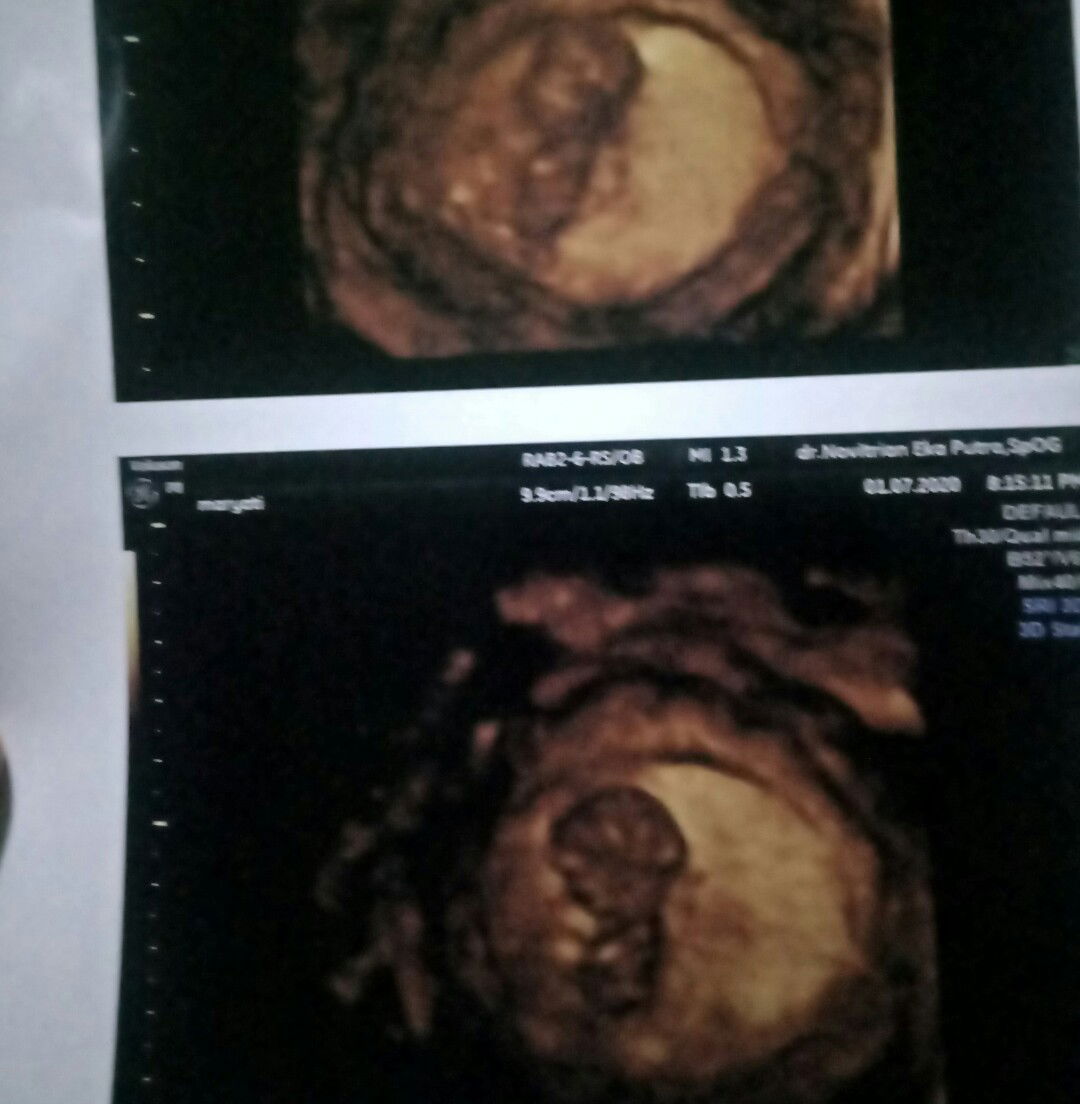

Tensi tinggi aj

Kadang grogi bisa bikin tensi tinggi bun